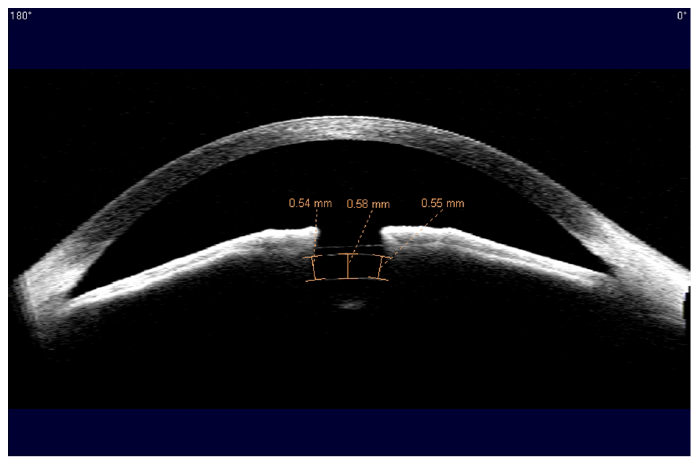

▼내원 당시 내피세포 검사 결과

이분의 경우, 렌즈 한쪽이 고정이 안되면서 눈을 깜빡일 때마다 눈을 자극했고, 그 결과 내피세포가 상당히 손상이 되었습니다. 당시 병원에 오셨을 때 내피세포는 1000개 초반이었습니다. 방치됐더라면 눈에 어떤 문제가 진행되고 있는지, 알지 못하고 계셨을지도 모릅니다. 부작용은 수술 자체가 아니라 수술 후 관리를 소홀히 했을 때 발생한다는 사실을 다시 한번 깨닫게 했던 사례였습니다.